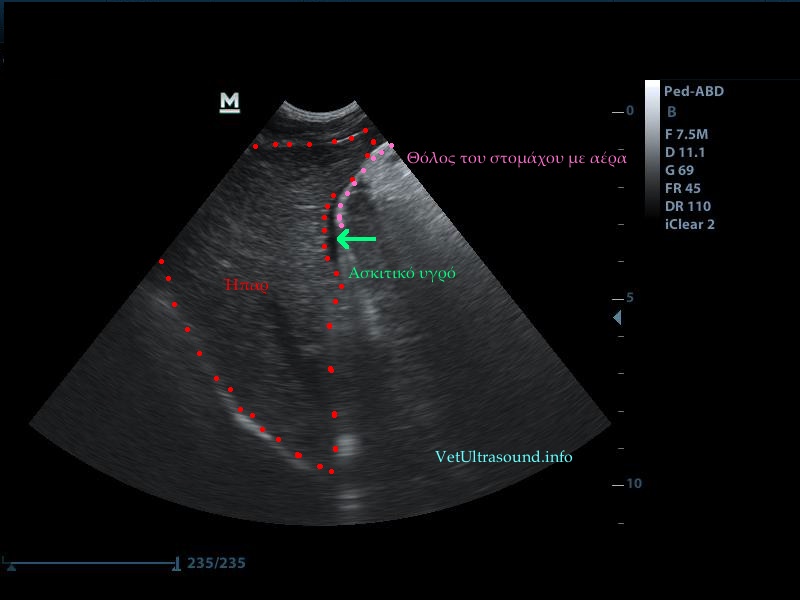

Διάγνωση: Ο σπλήνας ελέγχθηκε διογκωμένος και διάχυτα υποηχογενής χωρίς εστιακές αλλοιώσεις στο παρέγχυμά του. Το μεσεντέριο λίπος γύρω από αυτόν ήταν αρκετά υπερηχογενές και βρέθηκε μικρή παρουσία ασκιτικού υγρού ανάμεσα από τις εντερικές έλικες. Το έγχρωμο Doppler δεν έδειχνε αιμάτωση του σπλήνα και ιδιαίτερα των μεγάλων αγγείων. Η διάγνωση τέθηκε ως συστροφή σπλήνα και ο ασθενής οδηγήθηκε στο χειρουργείο.

– Το υπερηχογενές λίπος στην προκειμένη περίπτωση οφείλεται στην συστροφή των αγγείων και του λίπους με τη σειρά του στη πύλη του σπλήνα.

– Ο σπλήνας εμφανίζεται έτσι λόγω του οιδήματος που δημιουργείται από την παθητική συμφόρηση εξαιτίας του στραγγαλισμού των αρτηριών και των φλεβών που των αιματώνουν.